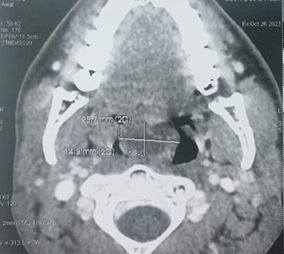

computed tomography (CT) scan of the of face revealed a mass of cystic density

filling the lumen of the nasopharynx and the upper part of the oropharynx which

was non-enhanced after contrast injection. However, all the paranasal sinuses

were clear (Figure 2). MRI of the

Figure 2. Axial and sagittal sections of a CT scan of the face: shows a mass of cystic density which is inserted into the middle turbinate and extends into the nasopharynx (a,b) and oropharynx (a,b,c).